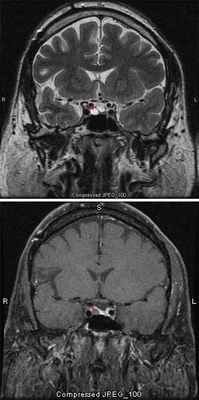

Компьютерная томография. Разработка компьютерной томографии (КТ-сканпрование) изменило диагностические мероприятия при множестве видов внутричерепной (и внечерепной) патологии и позволила заменить инвазивные методы, например артериографию и пневмоэнцефалографию, на неинвазивные. Использование контрастных веществ, вводимых внутривенно либо непосредственно в СМЖ [133], еще более повысило точность КТ-сканирования. Область турецкого седла и супраселлярное пространство увидеть с помощью этого метода труднее, хотя более новые конструкции приборов обладают большей разрешающей способностью. Особую пользу КТ-сканирование приносит при анализе пара- и супраселлярного распространения опухолей гипофиза, а также при определении СМЖ в турецком седле (синдром «пустого» турецкого седла). Окончательное значение этого метода следует оценивать по тому, насколько информация, получаемая с его помощью, позволяет избежать необходимости предоперационной ангиографии и/или пневмоэнцефалографии.

МРТ со срезами толщиной 1 мм

Вопрос об исключении опухоли гипофиза ставят при наличии головных болей, характерных расстройств зрения и эндокринопатии. Проводят нейровизуализационные исследования с толщиной среза 1 мм. МРТ более чувствительна, чем КТ, особенно для выявления микроаденом.